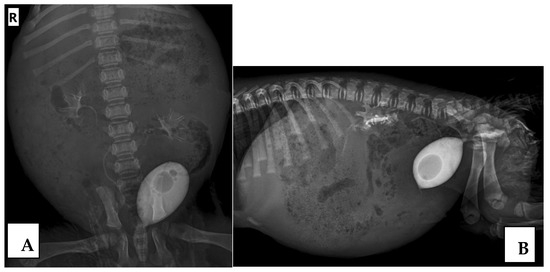

2.2.2. Contrast Retrograde Cystourethrography (RCUG)

2.3. VUR Assessment